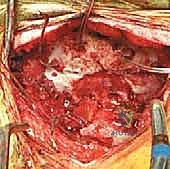

المرحلة الخامسة: التطعيم العظمي والدمج (Bone Grafting)

التثبيت المعدني وحده لا يكفي على المدى الطويل؛ يجب أن تلتحم العظام معًا. يقوم الجراح بوضع طعوم عظمية (تؤخذ عادة من حوض المريض، أو يتم استخدام طعوم صناعية/من بنك العظام) حول المنطقة المثبتة. مع مرور الأشهر، ينمو العظم الجديد فوق هذه الطعوم، مما يخلق جسرًا عظميًا صلبًا يربط الجمجمة بالرقبة بشكل دائم.